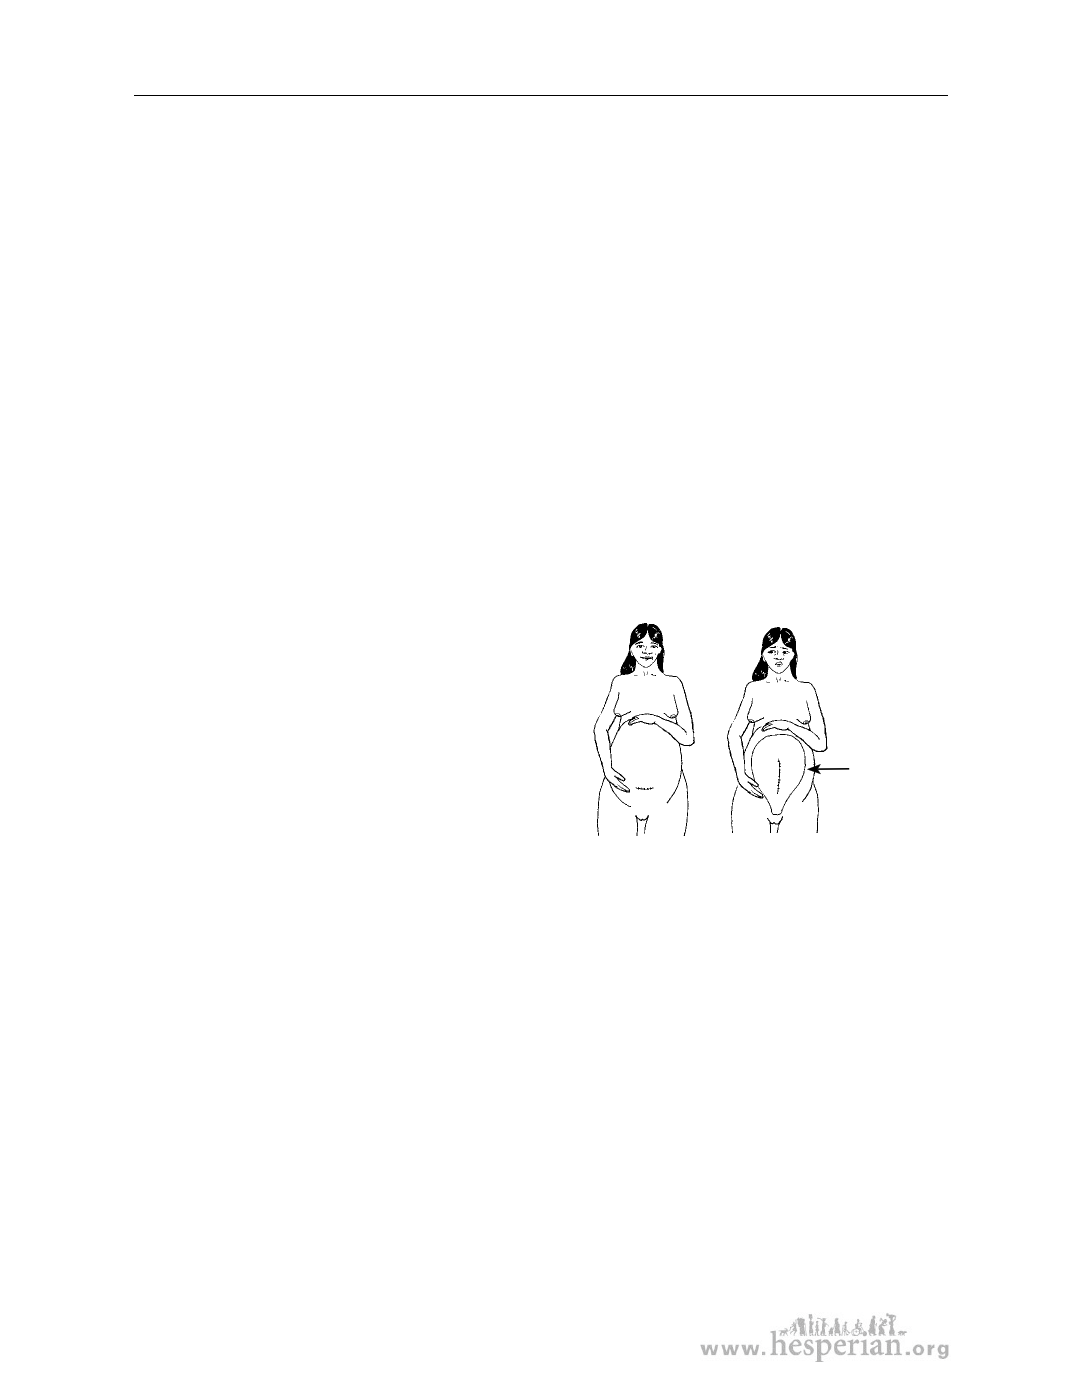

A scar on the

womb like this

is more likely

to open up in

Even though a c-section is sometimes

labor.

necessary, if possible it is best to avoid

A scar that

...may be hiding a scar

goes one way on on the womb that goes

the outside...

another way.

Many women who have had a baby delivered by c-section are able to give birth

the next time through the vagina. This is especially true if the cut from the c-section

was made across the lower belly from side to side, and not up and down. An up-

and-down scar is more likely to open up during labor.